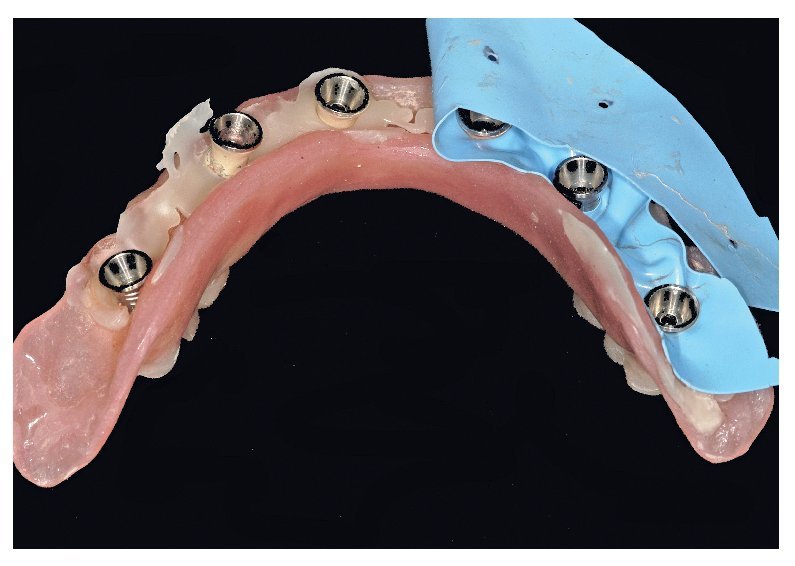

Tras una fase de curación sin complicaciones, se esperaron otros dos meses antes de ajustar las prótesis provisionales a las condiciones ahora estables de la mucosa. Se rebasaron los espacios intermedios formados a causa de la detumescencia del tejido blando tras la intervención, a fin de reducir o incrementar el volumen del cuerpo de la prótesis conforme a las indicaciones funcionales, higiénicas, fonéticas y estéticas, así como teniendo permanentemente en cuenta la oclusión. Una vez concluida esta fase pueden tomarse las impresiones para la restauración definitiva (figs. 75 a 79). Para la restauración de puente planificada, se toman las impresiones a nivel del implante.

Fig. 76. La toma de impresión definitiva en el maxilar superior tiene lugar a la altura del hombro del implante.

Fig. 77. La toma de impresión definitiva en el maxilar inferior tiene lugar a la altura del hombro del implante.

Fig. 78. Vista detallada de la impresión del maxilar superior.

Fig. 79. Vista detallada de la impresión del maxilar inferior.